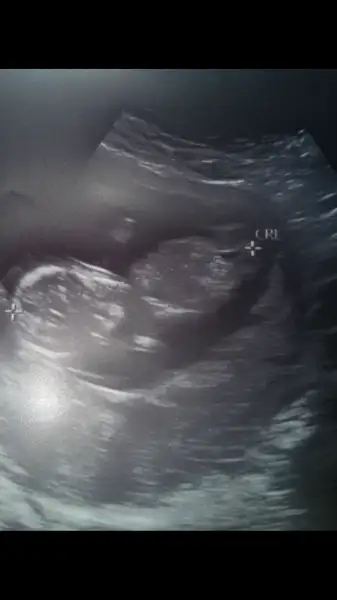

Kızlar bir nub daha bakın bana 11 +6 burda

2017-07-27 14.16.39.webp